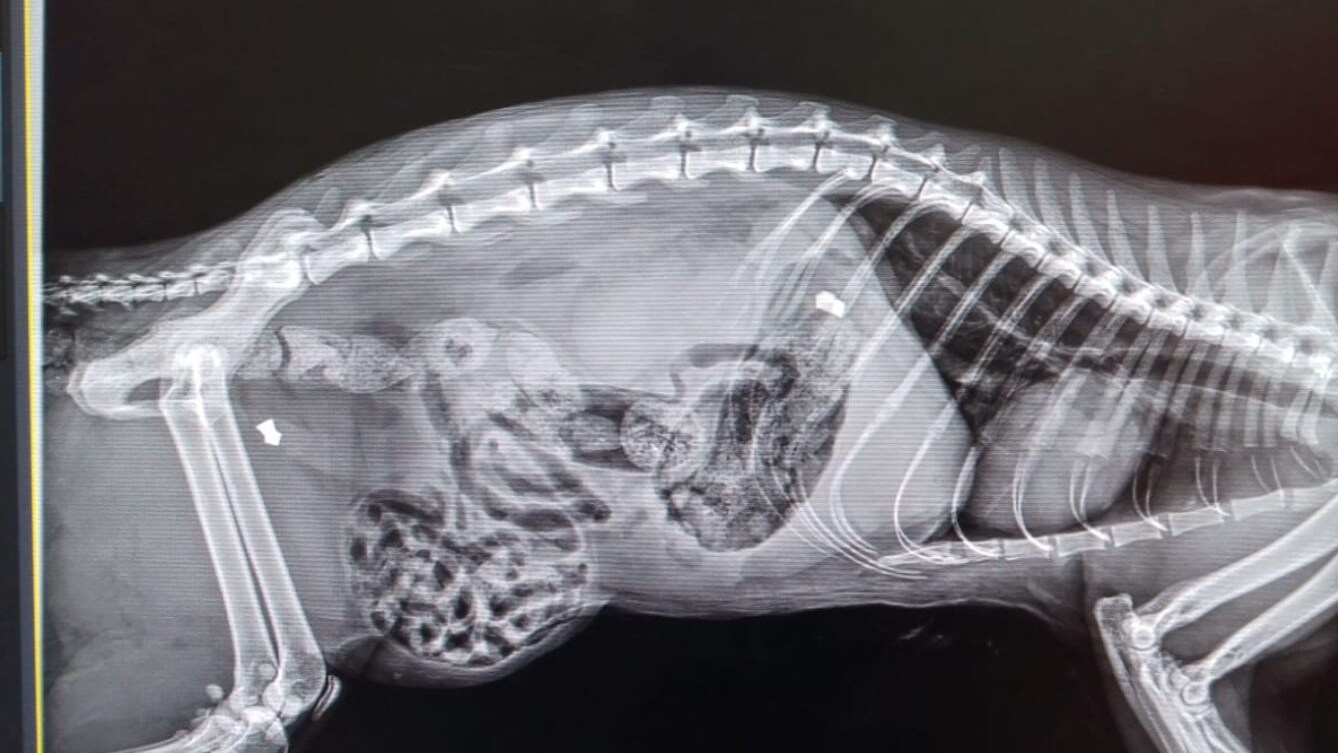

I fatti risalgono al 14 luglio: allertata dai lamenti insopportabili di un felino, una donna era uscita di casa aveva controllato i bidoni della spazzatura dei suoi vicini scoprendo in uno una micia molto sofferente, Lanna di 1 anno, che era stata massacrata dal suo pet mate morendo dopo poco. Secondo le dichiarazioni di Dode fatte al giudice, le persone con cui viveva la gatta avevano un figlio autistico che con lei si comportava in modo inappropriato. «Un giorno, l'animale lo ha graffiato e il papà ha perso la pazienza. Lo ha colpito a morte – spiega – Lanna è stata presa a pugni più volte e ripetutamente colpita alla testa con un asse di legno».